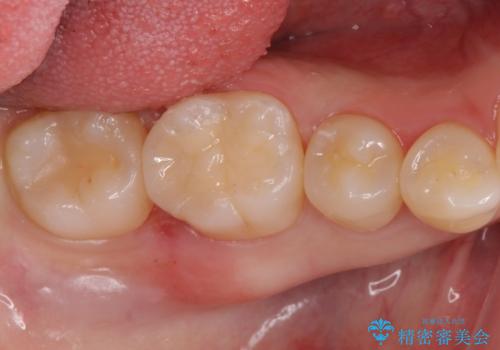

銀歯を白くしたい

担当医 岡田康成

目立つ銀歯を白くしたい ジルコニアクラウンでの修復